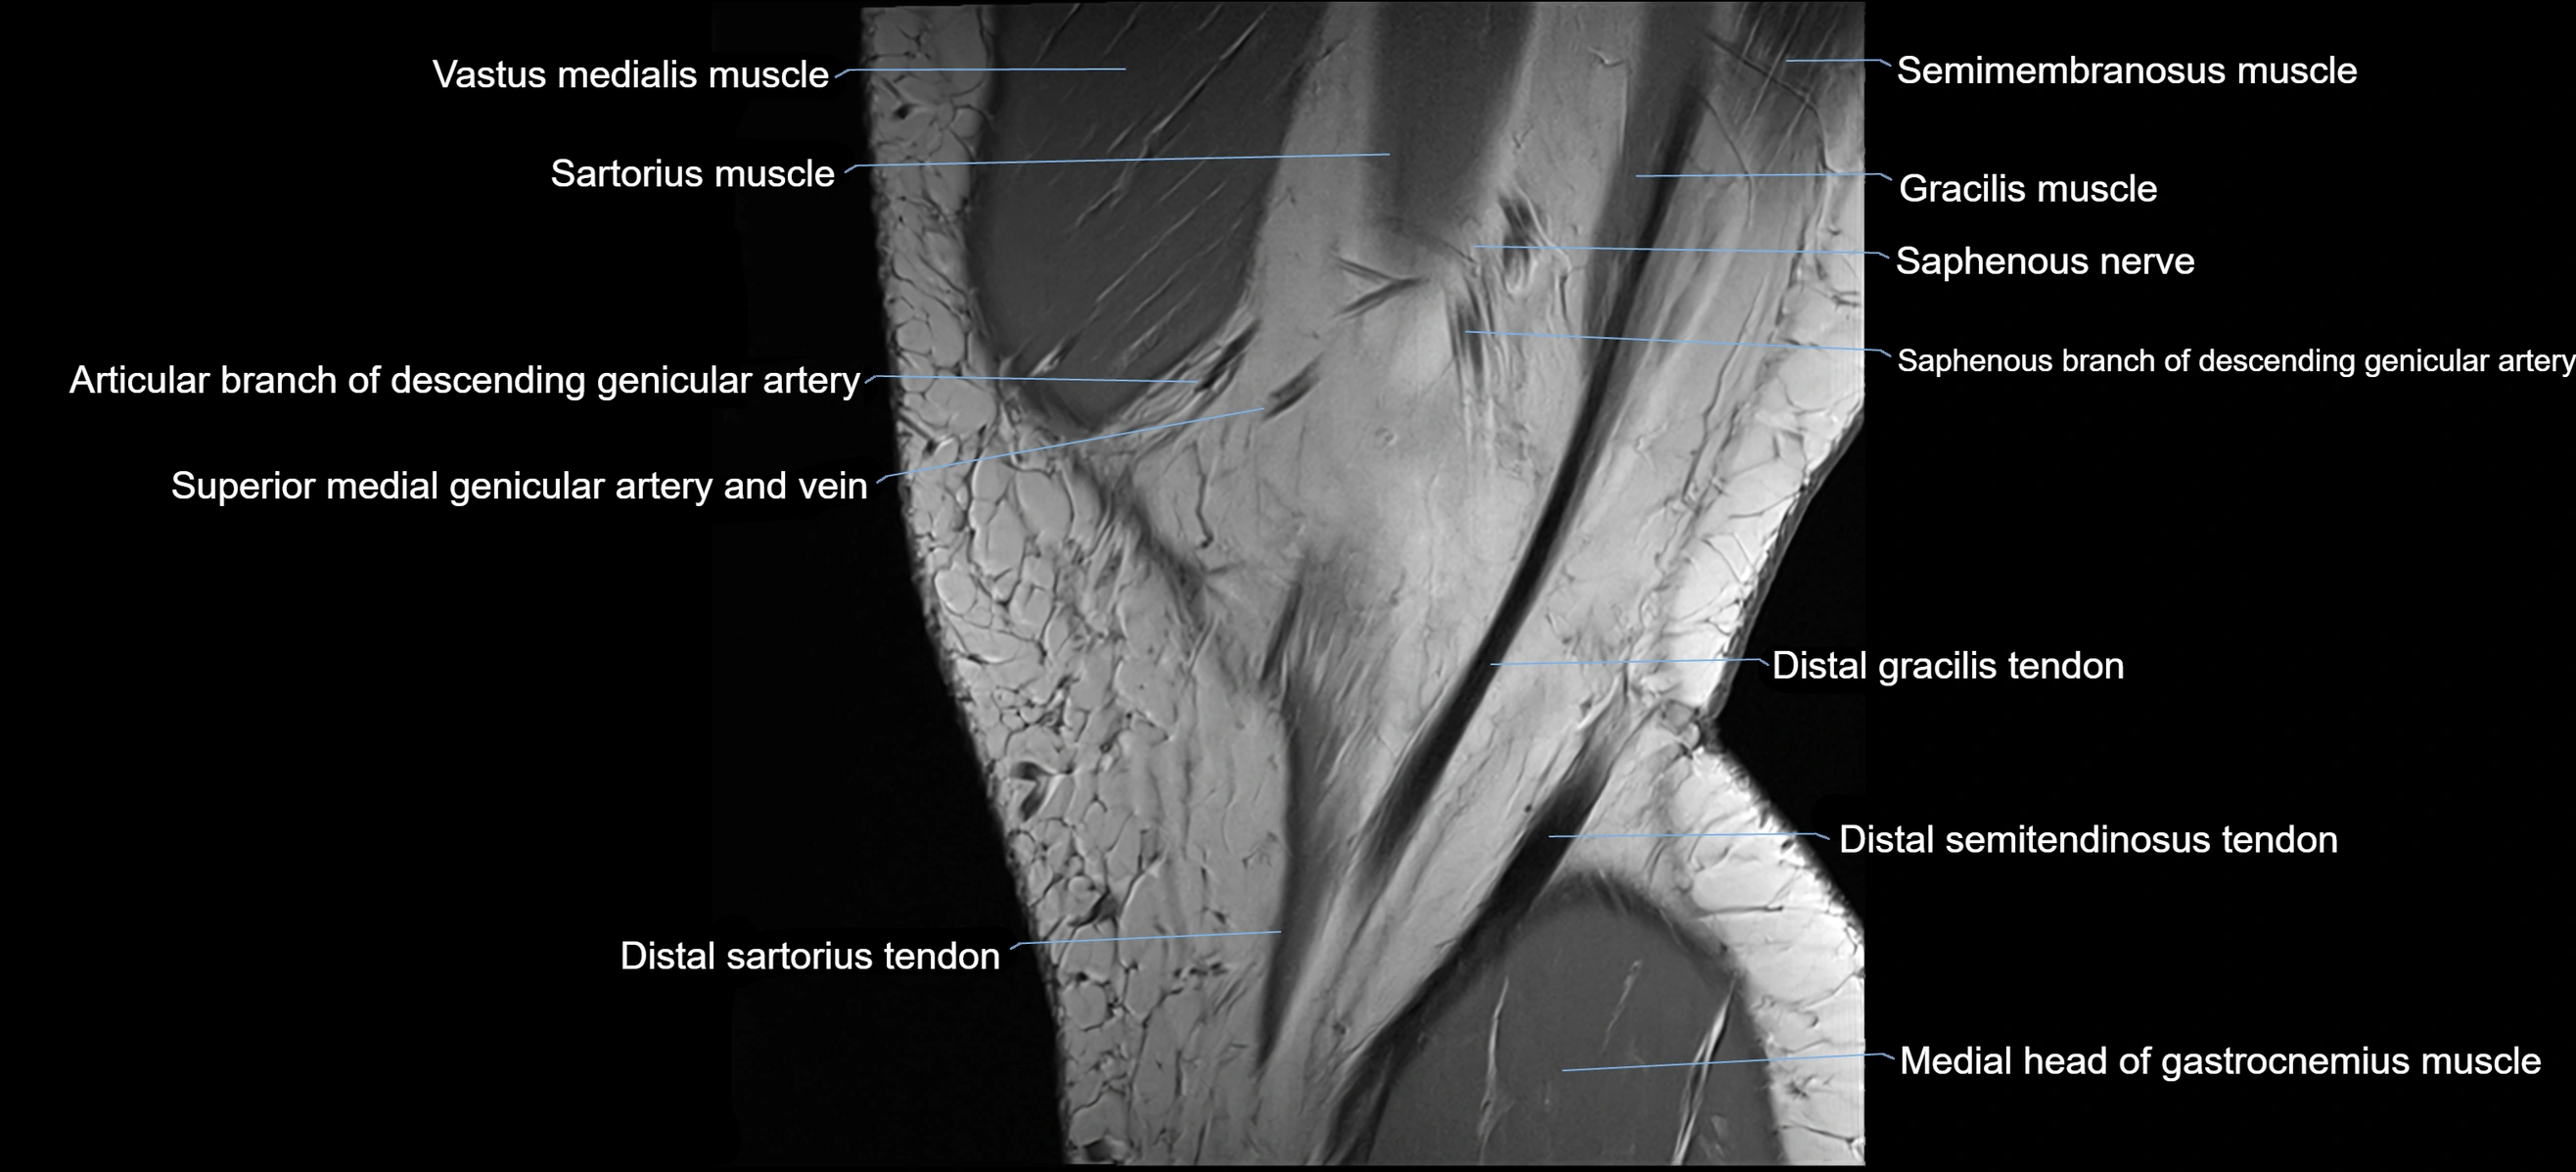

- Descending genicular artery (Saphenous branch)

- Gracilis tendon (Distal)

- Medial gastrocnemius tendon

- Medial head of gastrocnemius muscle

- Sartorius muscle

- Sartorius tendon (Distal)

- Semimembranosus muscle

- Superior medial genicular artery